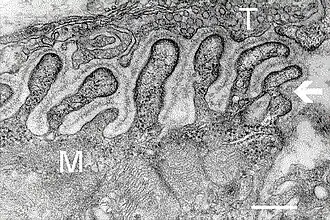

В нервно-мышечной системе нервы центральной нервной системы и периферической нервной системы связаны и работают вместе с мышцами[1]. Нервный отросток подходя к сарколемме мышечного волокна утрачивает миелиновую оболочку и образует сложный аппарат с плазматической мембраной мышечного волокна, образующийся из выпячиваний аксона и цитолеммы мышечного волокна, создавая глубокие «карманы». Синаптическая мембрана аксона и постсинаптическая мембрана мышечного волокна разделены синаптической щелью. В этой области мышечное волокно не имеет поперечной исчерченности, характерно скопление митохондрий и ядер. Терминали аксонов содержат большое количество митохондрий и синаптических пузырьков с медиатором ацетилхолином.